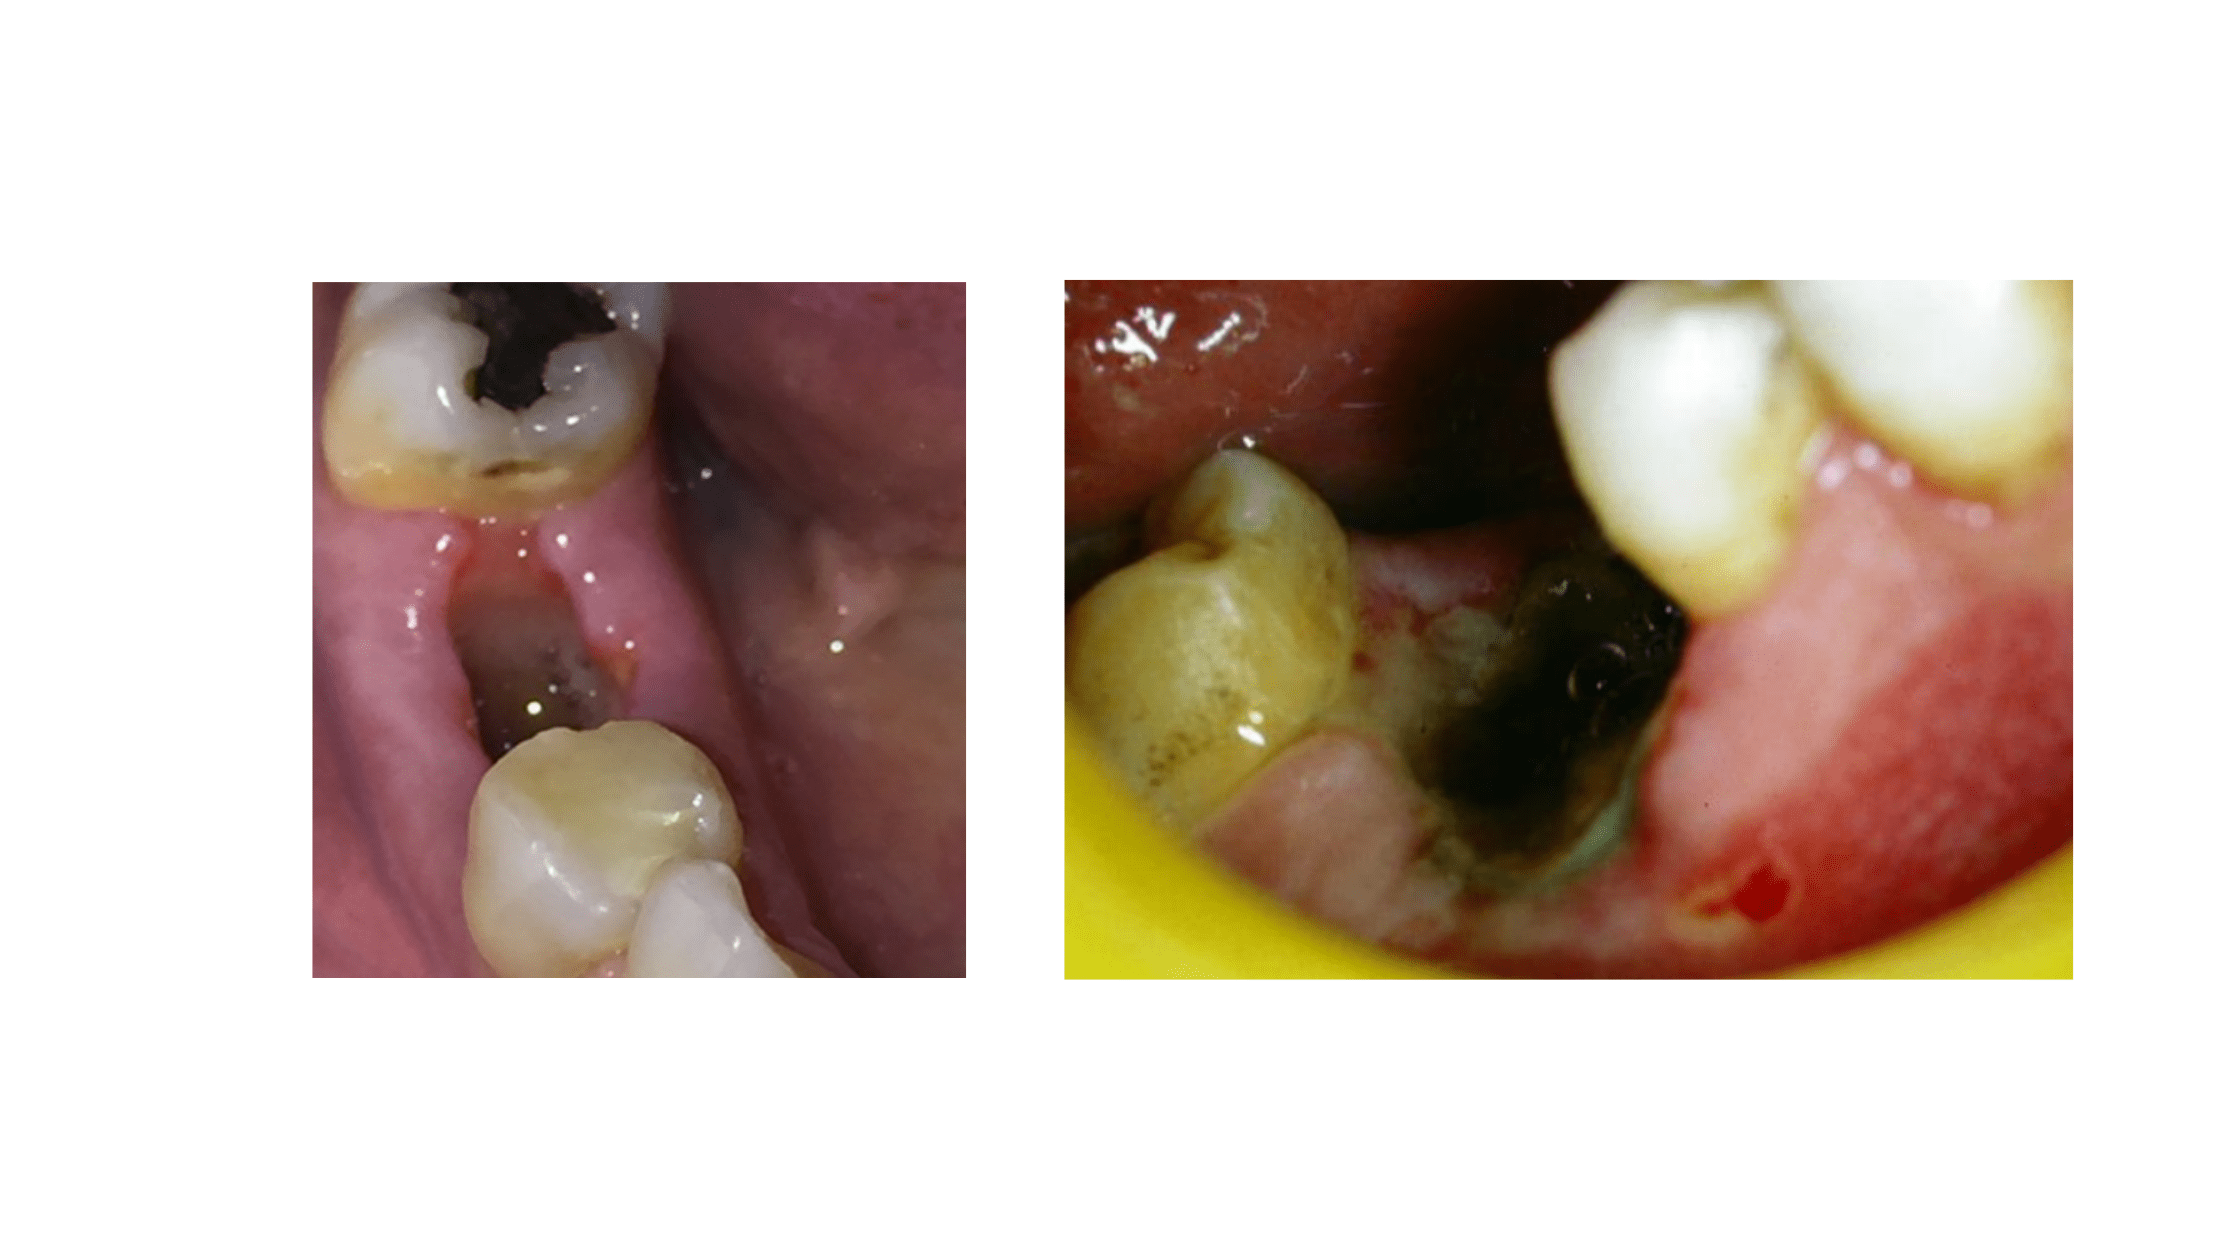

Dry Socket The Most Common Complication After Tooth Extraction

Socket Infection After Tooth Extraction What You Should Know